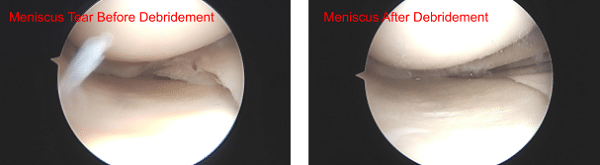

A lateral anterior entry portal was made and the arthroscopy was inserted. A medial anterior portal was made using a spinal needle. Examination of the medial tibial compartment showed a radius tear of the posterior body of the posterior horn of the medial meniscus. Resection of the margins of the tear was performed with the use of biters and shavers which achieved balanced margins.

There was also a horizontal tear which was debrided. Balanced margins would be achieved. There was Grade III to Grave IV osteoarthritis of the medial femoral condyle. Examination of the infrapatellar notch showed an intact ACL.

Meniscus before and after Debridement